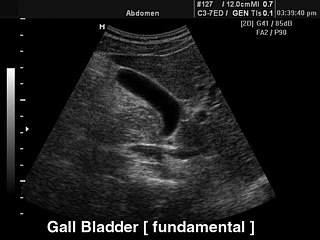

Fundamental harmonic (базовая гармоника)

УЗИ желчного пузыря.